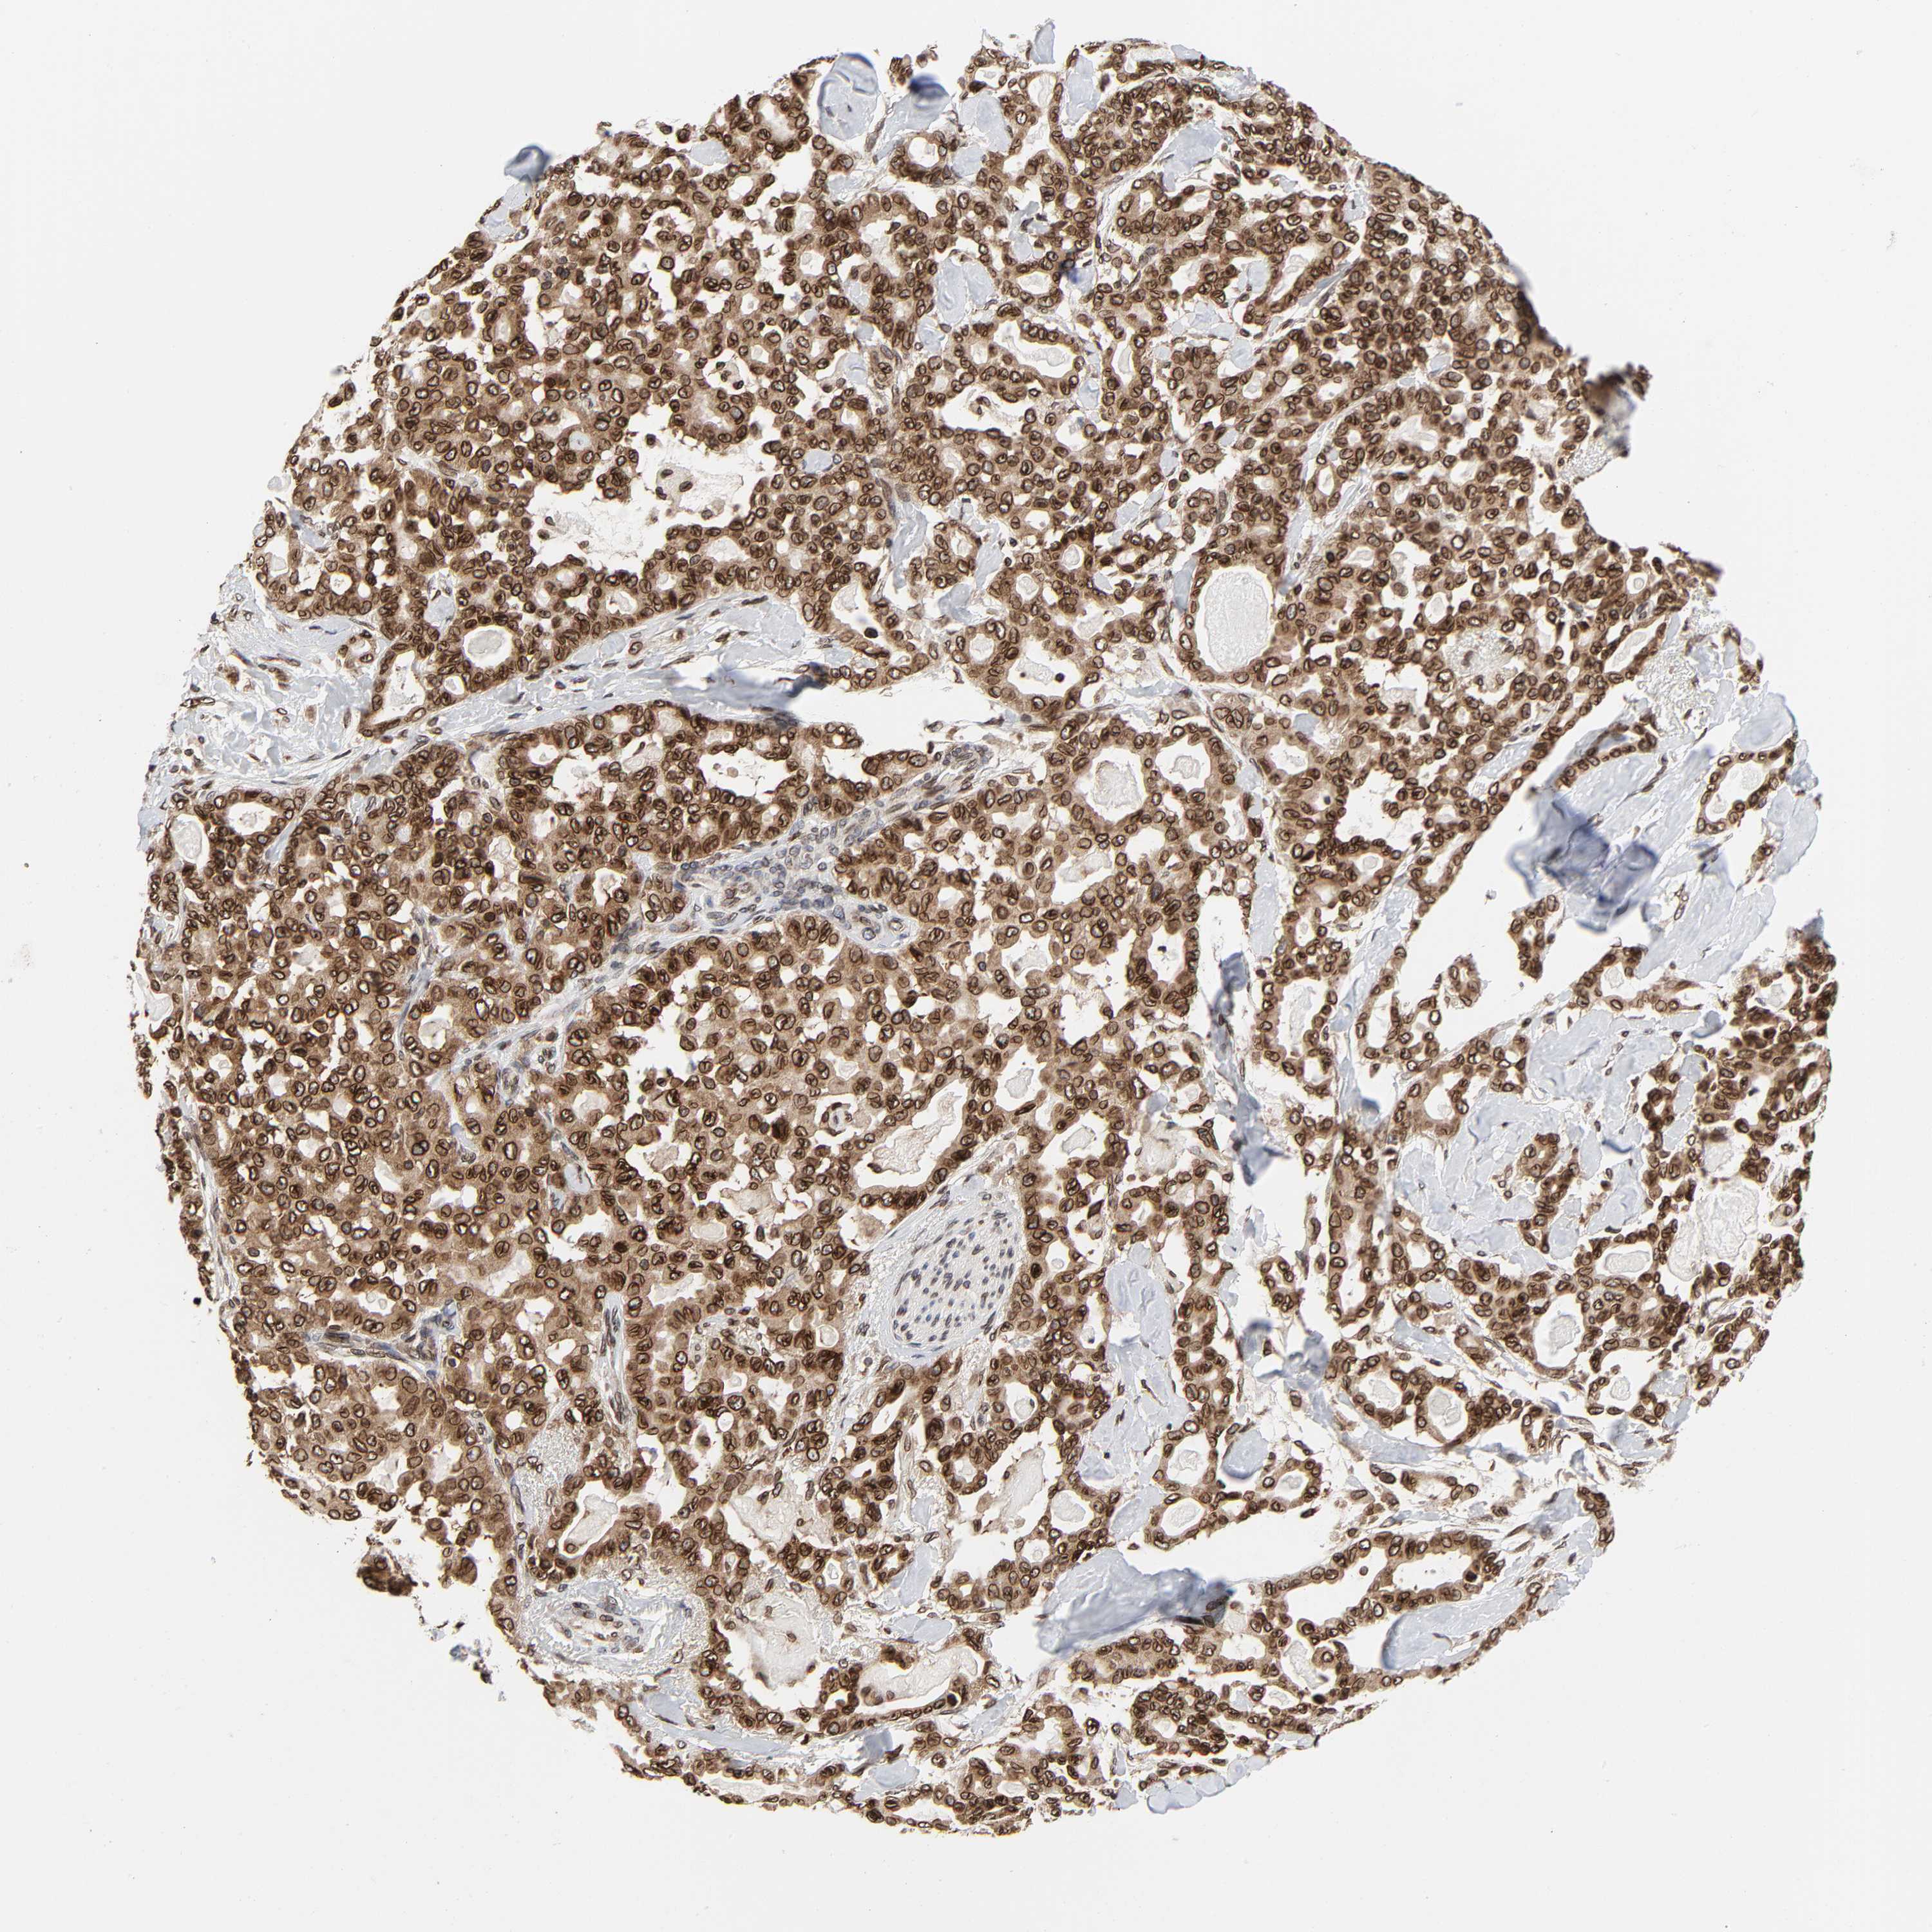

PANCREATIC CANCER - Protein expressioni

A mouse-over function shows sample information and annotation data. Click on an image to view it in a full screen mode. Samples can be filtered based on level of antibody staining by selecting one or several of the following categories: high, medium, low and not detected. The assay and annotation is described here.

Note that samples used for immunohistochemistry by the Human Protein Atlas do not correspond to samples in the TCGA dataset.

Antibody stainingi

Antibody staining in the annotated cell types in the current human tissue is reported as not detected, low, medium, or high, based on conventional immunohistochemistry profiling in selected tissues. This score is based on the combination of the staining intensity and fraction of stained cells.

Each image is clickable and will lead to virtual microscopy that enables deeper exploration of all samples and also displays staining intensity scores, fraction scores and subcellular localization as well as patient and tissue information for each sample.

Antibody HPA050110

Antibody CAB004293

Staining

High

Medium

Low

Not detected

Intensity

Strong

Moderate

Weak

Negative

Quantity

>75%

75%-25%

<25%

None

Location

Nuclear

Cytoplasmic/membranous

Cytoplasmic/membranous,nuclear

Adenocarcinoma, NOS

Adenocarcinoma, metastatic, NOS